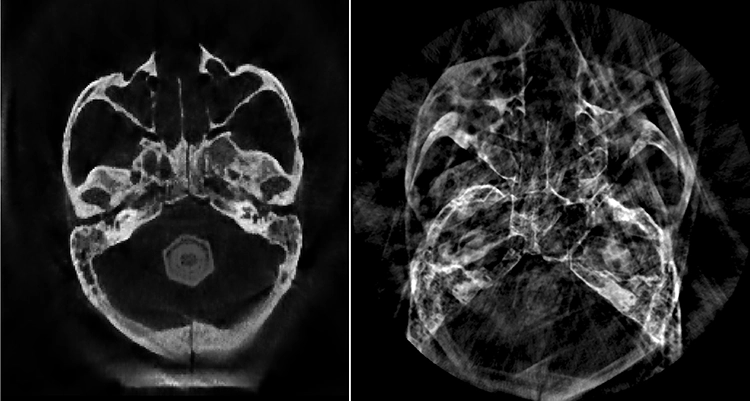

Diese Verfahren haben gegenüber den Einschrittverfahren, die letztlich die physikalischen Prozesse der Röntgenprojektion invertieren (Radon-Inversion) [4], den wesentlichen Vorteil, qualitativ bessere Lösungen vor allem bei fehlerbehafteten Daten oder weniger Projektionsaufnahmen zu ermöglichen. Letzteres ist ein beliebter Ansatz zur Dosisreduktion, d.h. zu den heute häufig implementierten „Low-Dose-Protokollen“. Zur Verwacklungskorrektur gibt es bereits sehr gute Verfahren, die ohne jegliche Referenzkörper auskommen und eine A-posteriori-Verbesserung der Daten ermöglichen (Abb. 1) [5]. Diese Änderungen betreffen die Software. Aber auch bei der Hardware gibt es eine Innovation, die die DVT revolutionieren wird: photonenzählende Detektoren (PCD).